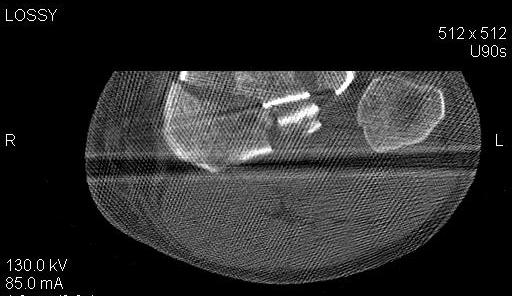

Пациенту сделали КТ - ухитрились сделать на шине Белера (не давал положить прямую ногу) - срезали передний отдел. Планируется на пятницу (24.12) на операцию - синтез  длинной мыщелковой LCP-пластиной Synthes :). Отек ближе к слову умеренный (окружность голени +4 см по сравнению со здоровой). КТ и снимок на вытяжении прилагаются.